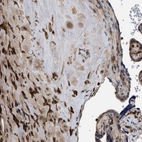

Immunohistochemical staining of human lymphoid node shows strong cytoplasmic/membranous positivity in non-germinal center cells.